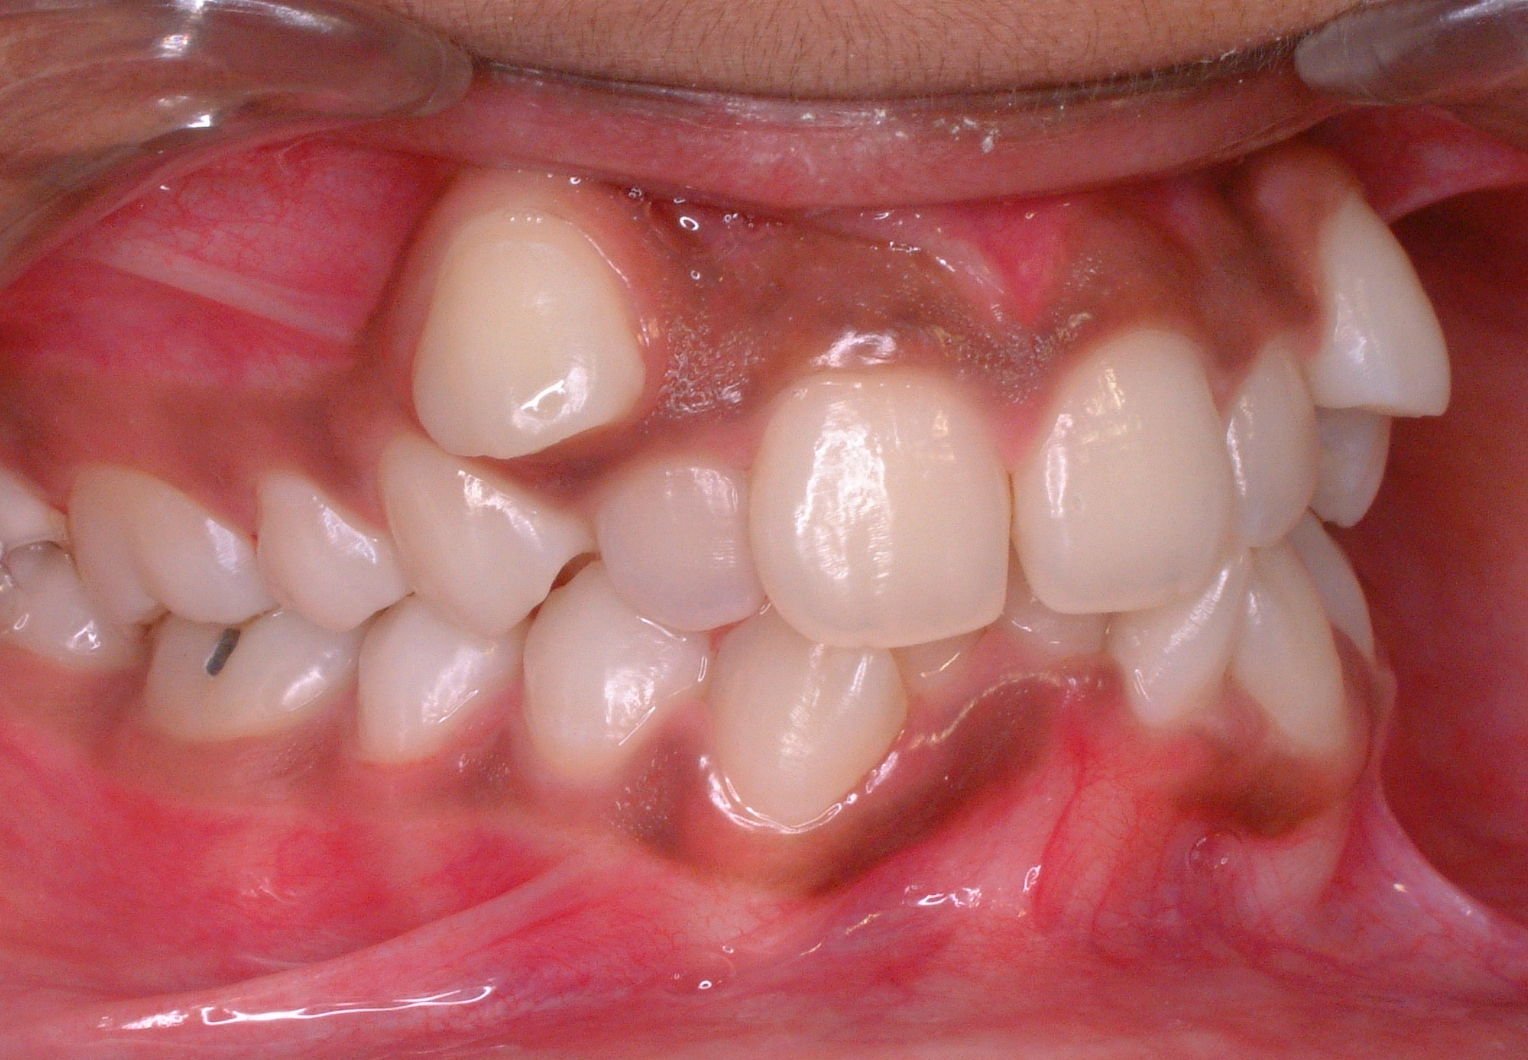

에드워드 앵글(Edward Angle)은 부정교합을 처음으로 분류한 사람으로, 그의 분류는 상악골(위턱뼈) 첫 번째 어금니의 상대적인 위치에 기초한다.[72] 앵글에 의하면 윗쪽 첫 번째 어금니의 앞 중앙쪽 볼 방향(mesiobuccal)이 아래턱뼈 어금니의 볼고랑(협측구)과 나란해야 한다.[72] 모든 치아들은 교합선에 맞아야 하는데, 이때의 교합선은 위턱뼈의 중심의 오목한 부분과 송곳니의 치대(齒帶), 아래턱뼈의 협측교두(뺨쪽 치아도드리)와 앞니 끝을 지나는 부드러운 곡선을 말한다.앵글 분류법에 따르면 부정교합은 다음과 같이 세 가지 유형으로 나눌 수 있다.[71]

- 1급 부정교합(중립 교합): 교합의 대구치 관계는 정상이나, 다른 치아에 공간, 총생, 과잉 또는 과소 맹출과 같은 문제가 있다.

- 2급 부정교합(원심 교합)([하악후퇴증], 과개, 과도한 수직 피개): 상악 제1대구치의 원심협측 교두가 하악 제1대구치의 원심협측구보다 전방에 위치한다. 2개의 아형이 있다.

- 2급 1분: 대구치 관계는 2급이며, 전방 치아가 돌출되어 있다.

- 2급 2분: 대구치 관계는 2급이지만, 중절치가 설측경사되어 있고, 측절치가 중절치를 덮고 있다.

- 3급 부정교합: (근심 교합)([하악전돌증], 전치부 반대교합, 음성 수평 피개, 과소 교합) 상악 대구치가 원심협측구에 위치하지 않고 그 뒤에 위치한다. 즉, 상악 제1대구치의 원심협측 교두는 하악 제1대구치의 원심협측구의 뒤에 위치한다. 이 경우 하악 전치가 상악 전치보다 더 두드러지게 보이는 경우가 많으며, 환자는 큰 하악골 또는 짧은 상악골을 가지고 있을 수 있다.